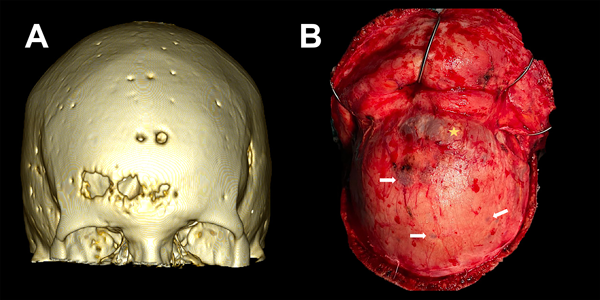

En el estudio de resonancia magnética (RM) de encéfalo se observó lesión extraaxial expansiva bifrontal con compromiso del seno frontal y tercio anterior de seno sagital superior de aspecto sólido e hipervascularizada, de aproximadamente 5.2 x 5.8 x 7.7 cm. Lesión isointensa en secuencia T1 e hipo-hiper intensa en secuencia T2, que realzaba de manera homogénea a la administración de contraste paramagnético con engrosamiento leptomeníngeo asociado. En secuencia FLAIR, se evidenció edema perilesional con colapso de las astas ventriculares frontales. En AngioRM se advirtió un gran aporte vascular de ambas arterias cerebrales anteriores, y en ventana ósea, múltiples lesiones osteolíticas en calota craneana (Figura 2).

Figura 3. Lesiones osteolíticas con componente exofítico transcraneano. A) TC con reconstrucción 3D de ventana ósea donde se evidencia calota erosionada por lesiones en sacabocado, características del mieloma múltiple. B) Correlación intraquirúrgica de lesión osteolítica y exofitica (estrella amarilla). Presencia de múltiples lesiones en sacabocado a nivel de la calota craneana (flechas blancas).

Se han descripto dos patrones de extensión, la diseminación hematógena de células plasmáticas y la diseminación continua directa desde lesiones líticas erosionadas del cráneo.1,12 En cuanto al diagnóstico diferencial, destacan las similitudes imagenológicas con los meningiomas, tumores que surgen de las células aracnoideas de la duramadre y constituyen una de las neoplasias intracraneales más comunes. En RM suelen verse como una masa extraaxial redondeada de bordes suaves y circunscrita con base ancha en la superficie dural, presentan hipointensidad en secuencia T1 e hiperintensidad en secuencia T2 con realce homogéneo a la administración de contraste y el signo de “cola dural” que no es patognomónico de esta entidad y puede advertirse en otras lesiones como hemangiopericitoma, metástasis o linfomas; esto hace casi indistinguible la diferenciación preoperatoria en casos como este (ver Figuras 1 y 2).